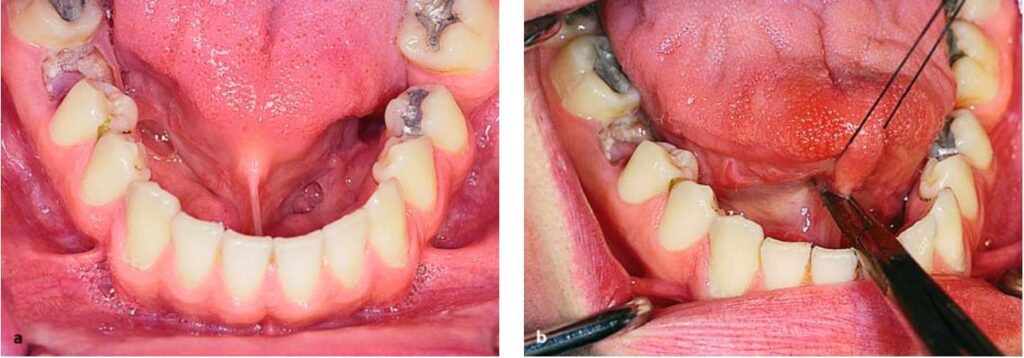

Ở hàm dưới, thắng lưỡi cũng có thể gây vấn đề, ví dụ như dính lưỡi, có thể hoàn toàn hoặc không hoàn toàn (H10.73).

Thắng lưỡi bám vào sàn miệng hoặc niêm mạc xương ổ, khi thắng lưỡi quá ngắn gây hạn chế vận động lưỡi và khó khăn trong việc phát âm.